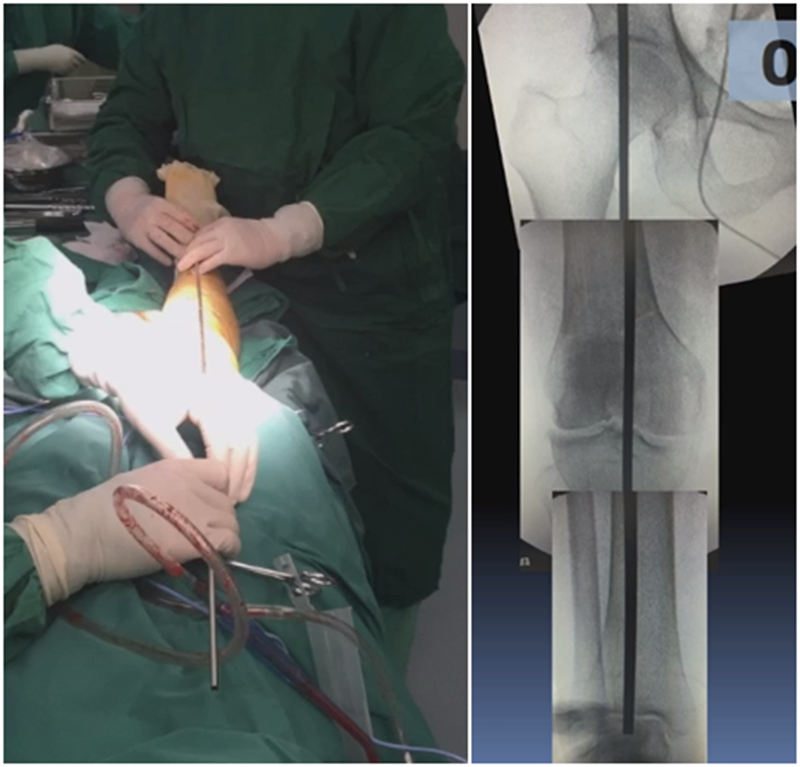

病例,X患者,女,双侧外翻膝,行双侧DFO。

术后6周摔伤,一侧出现膝内翻。

影像学检查显示左侧出现合页断裂。

进行翻修,术前力线显示内翻。

术中发现螺钉松动,截骨端出现坎插迹象。

近端螺钉松开,调整力线,重新固定后,在外侧加小钢板抗旋。

术后10周复查,力线较好。